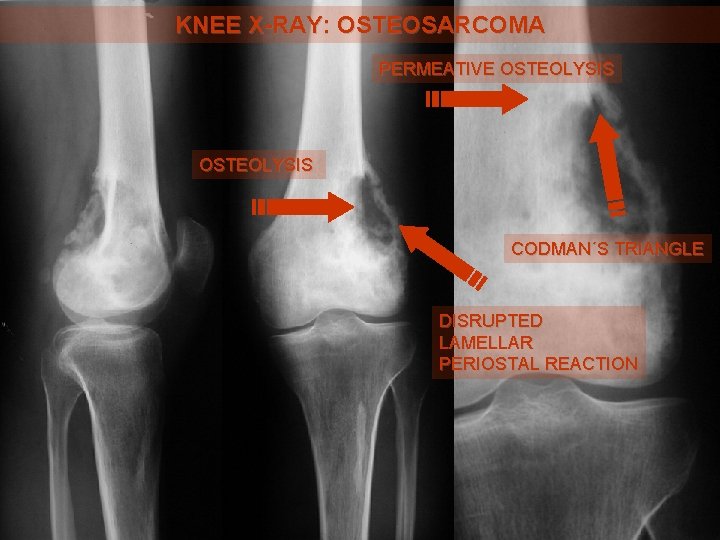

KNEE X-RAY: OSTEOSARCOMA PERMEATIVE OSTEOLYSIS CODMAN´S TRIANGLE DISRUPTED LAMELLAR PERIOSTAL REACTION